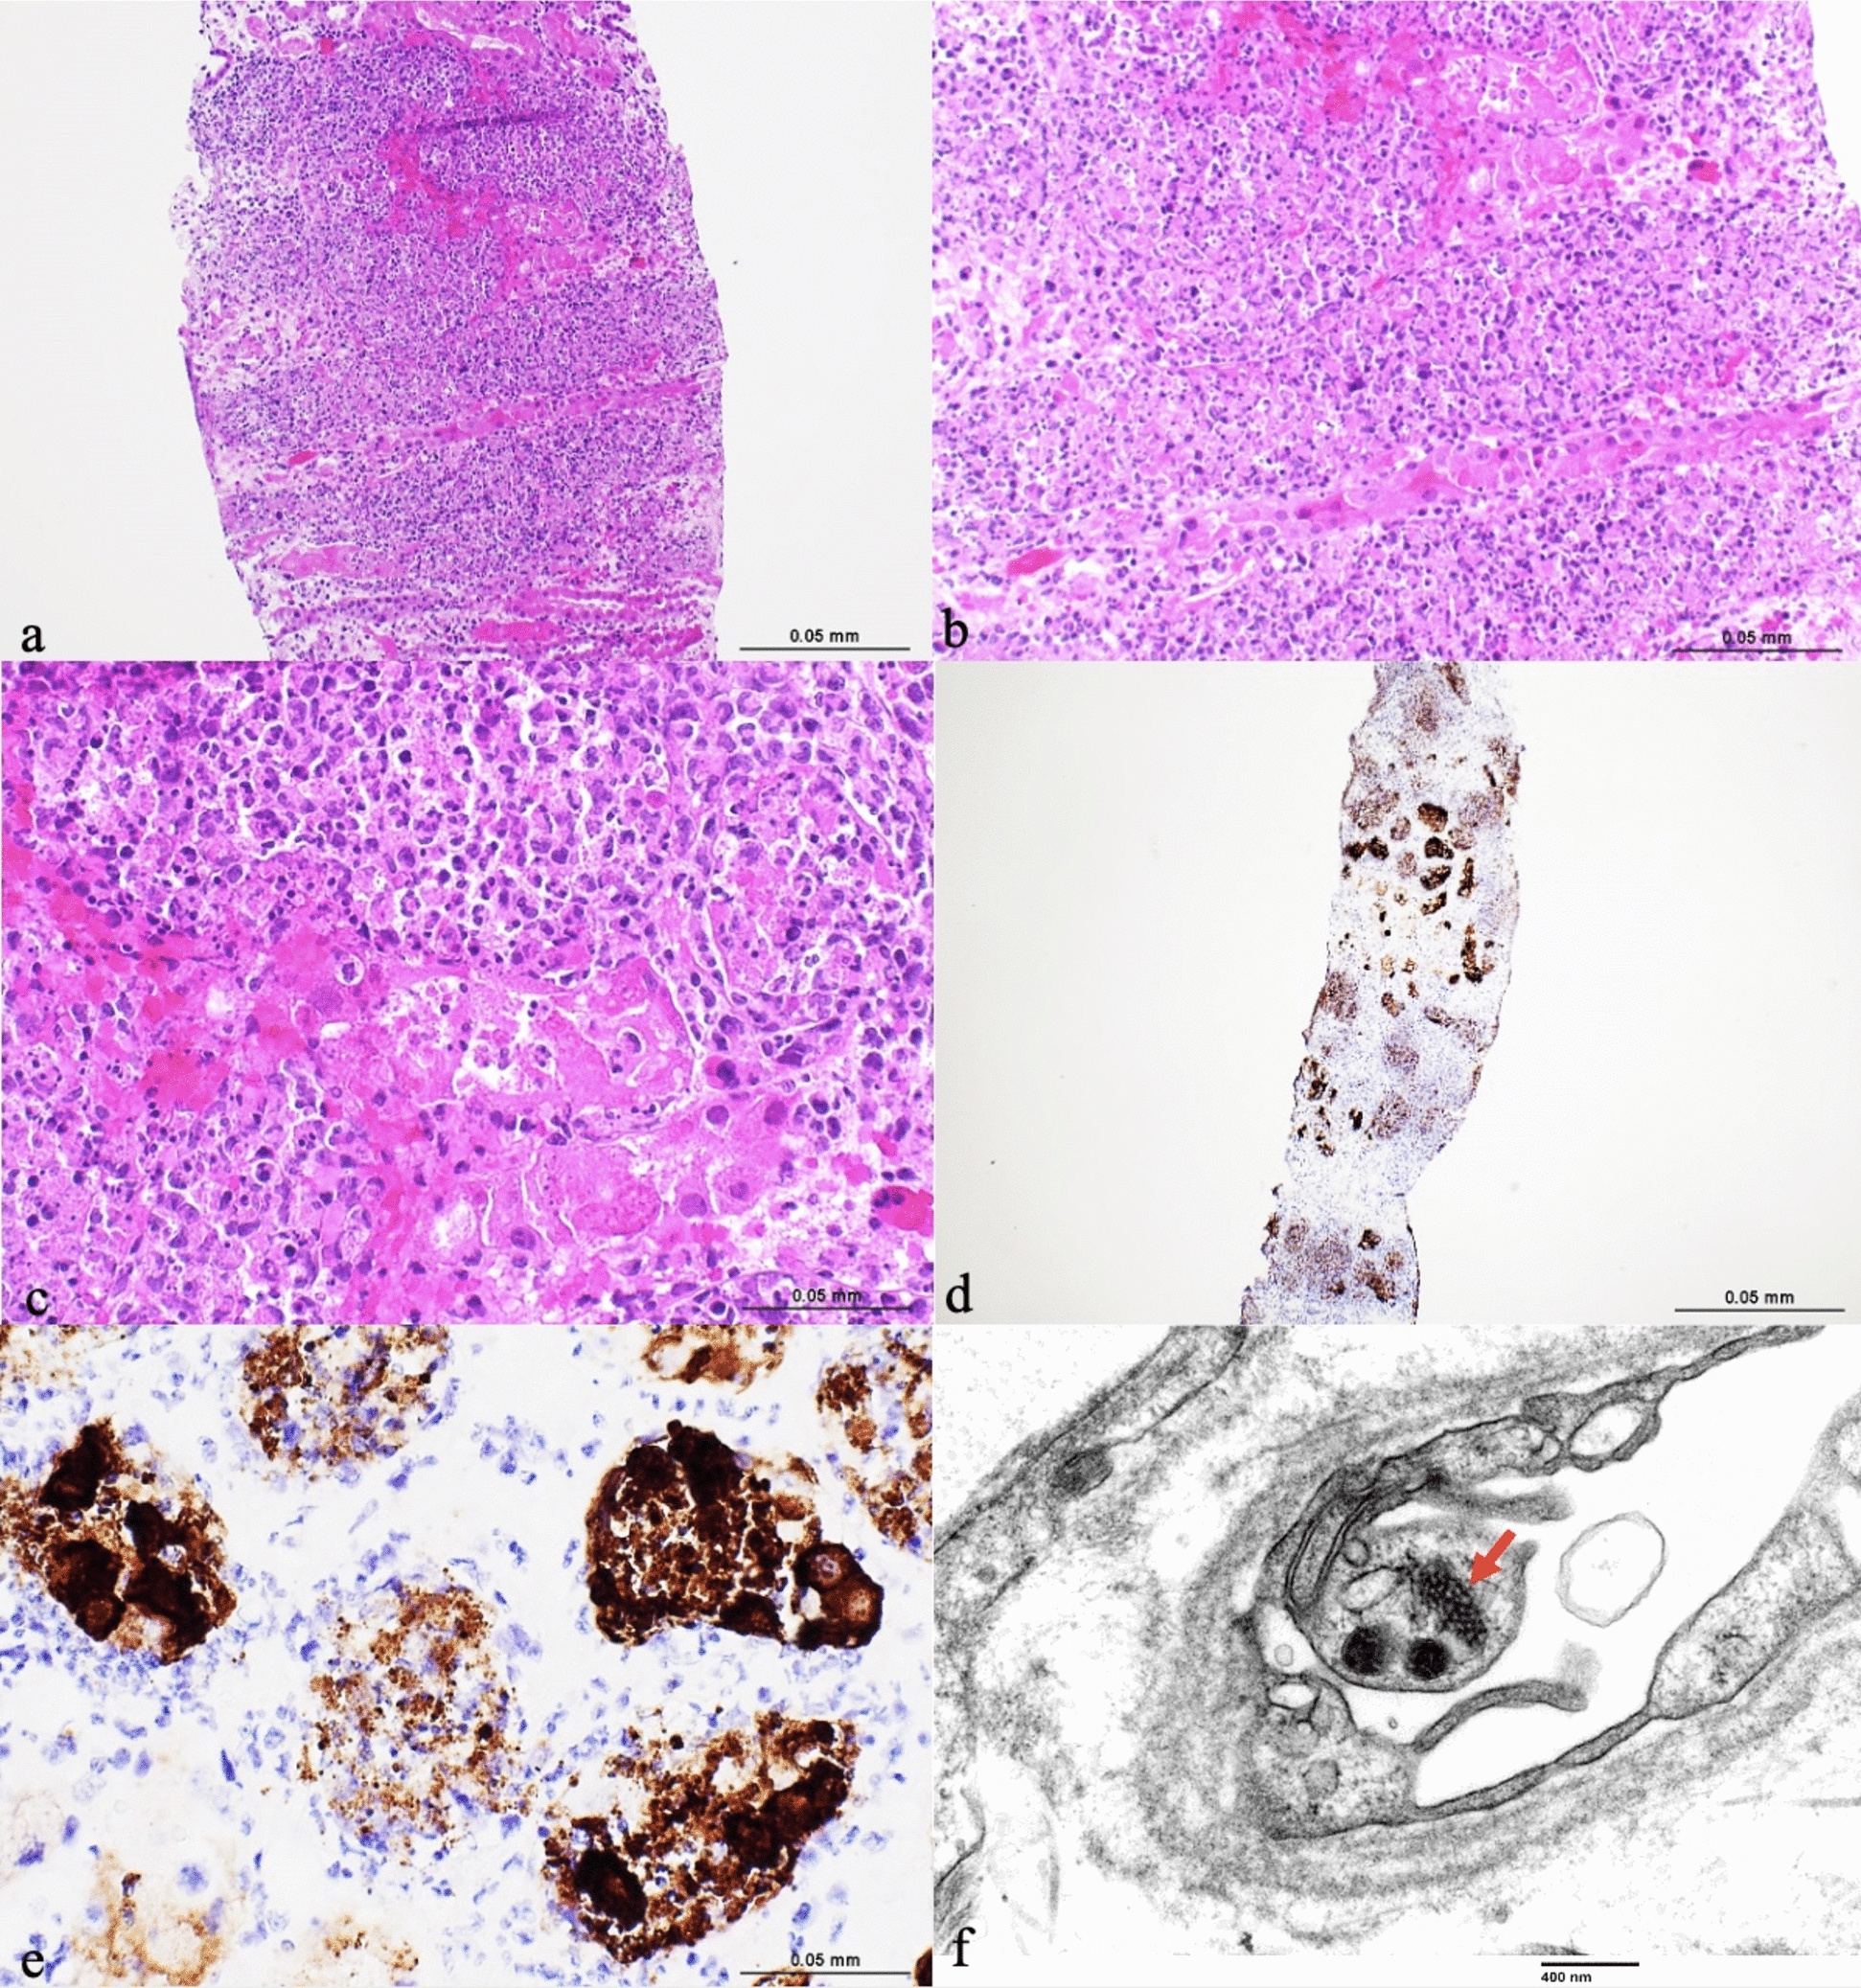

Human adenovirus is a double-stranded, non-enveloped DNA virus that can cause infection in kidney transplant recipients, with a spectrum of symptoms ranging from asymptomatic viremia to disseminated disease. Adenovirus nephritis typically presents with fever and hemorrhagic cystitis. It can cause an inflammatory response but rarely results in allograft failure [1]. Standard treatment options consist of immunosuppression reduction with consideration given to the use of cidofovir. Adenovirus-specific T-cell infusions have shown promise in therapeutic and prophylactic therapy in stem cell transplants but lack data in solid organs at this time [2]. The picture shows the kidney biopsy of a 32-year-old male with end-stage kidney disease secondary to diabetes mellitus type I, who received a simultaneous pancreas—kidney transplant. Induction therapy consisted of anti-thymocyte globulin and methylprednisolone. Maintenance therapy included tacrolimus, mycophenolate, and prednisone. At 3 weeks post-transplant, he reported generalized fatigue and diarrhea. Laboratory studies revealed leukocytosis, lymphopenia, and creatinine of 2.1 mg/dL (baseline 1.6–1.9 mg/dL). Urinalysis showed hematuria and pyuria. Respiratory viral panel, urine, and serum PCR for adenovirus were positive and the remaining infectious work-up including BK and CMV were negative. He received intravenous immunoglobulins (IVIG) and mycophenolate was held. He improved clinically and was discharged home but was readmitted with fevers and dysuria. Computed tomography abdomen/pelvis did not identify a source of infection. A kidney allograft biopsy showed interstitial edema, severe inflammation with neutrophils, micro abscesses, focal tubular necrosis, and interstitial hemorrhages (Fig. 1). Immunostaining for adenovirus antigen in the tubular epithelial cells confirmed the infection. He had a rapid rise in serum adenovirus PCR from < 200 to 338,844 copies/mL despite decreasing immunosuppression and IVIG treatment. He was ultimately treated with cidofovir. Serum PCR levels declined steadily, with improvement of creatinine to baseline. He was subsequently admitted with elevated pancreatic enzymes with a concern for rejection versus adenovirus pancreatitis versus cidofovir-induced pancreatitis. Imaging was normal. Biopsy was deferred and he improved with conservative management.

Fig. 1

Severe diffuse neutrophil-rich interstitial inflammation, tubular injury, and focal cortical hemorrhagic necrosis a Hematoxylin–eosin ×100; b Hematoxylin–eosin ×200; c Hematoxylin–eosin ×400; d Immunostaining for adenovirus ×40 shows abundant tubulointerstitial positivity; e immunostaining for adenovirus ×400; f tubuloreticular inclusions in peritubular capillary endothelial cell (transmission electron microscopy, ×46,700)